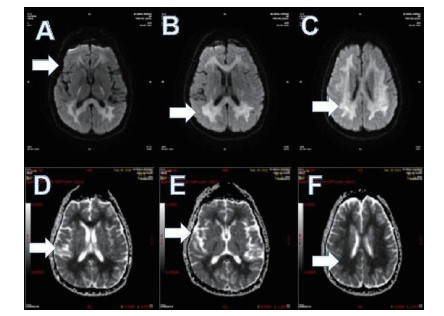

磁共振提示胼胝体局灶病变多为轻症患者(图 3);磁共振提示胼胝体双侧放射冠部散在病变多为中型患者(图 4);磁共振提示胼胝体双侧放射冠区弥漫性病变多为重症患者(图 5,6)。

| 图 3 ABCD为同例患者,病变为胼胝体局灶病变(箭头所示);EFGH为同例患者,病变为胼胝体右侧放射冠区局灶病变(箭头所示) |

| 图 4 此图为中型患者,可见胼胝体双侧放射冠部散在病变 |

| 图 5 重型患者,可见胼胝体双侧放射冠区弥漫性病变 |

| 图 6 重型患者,可见胼胝体双侧放射冠区弥漫性病变 |